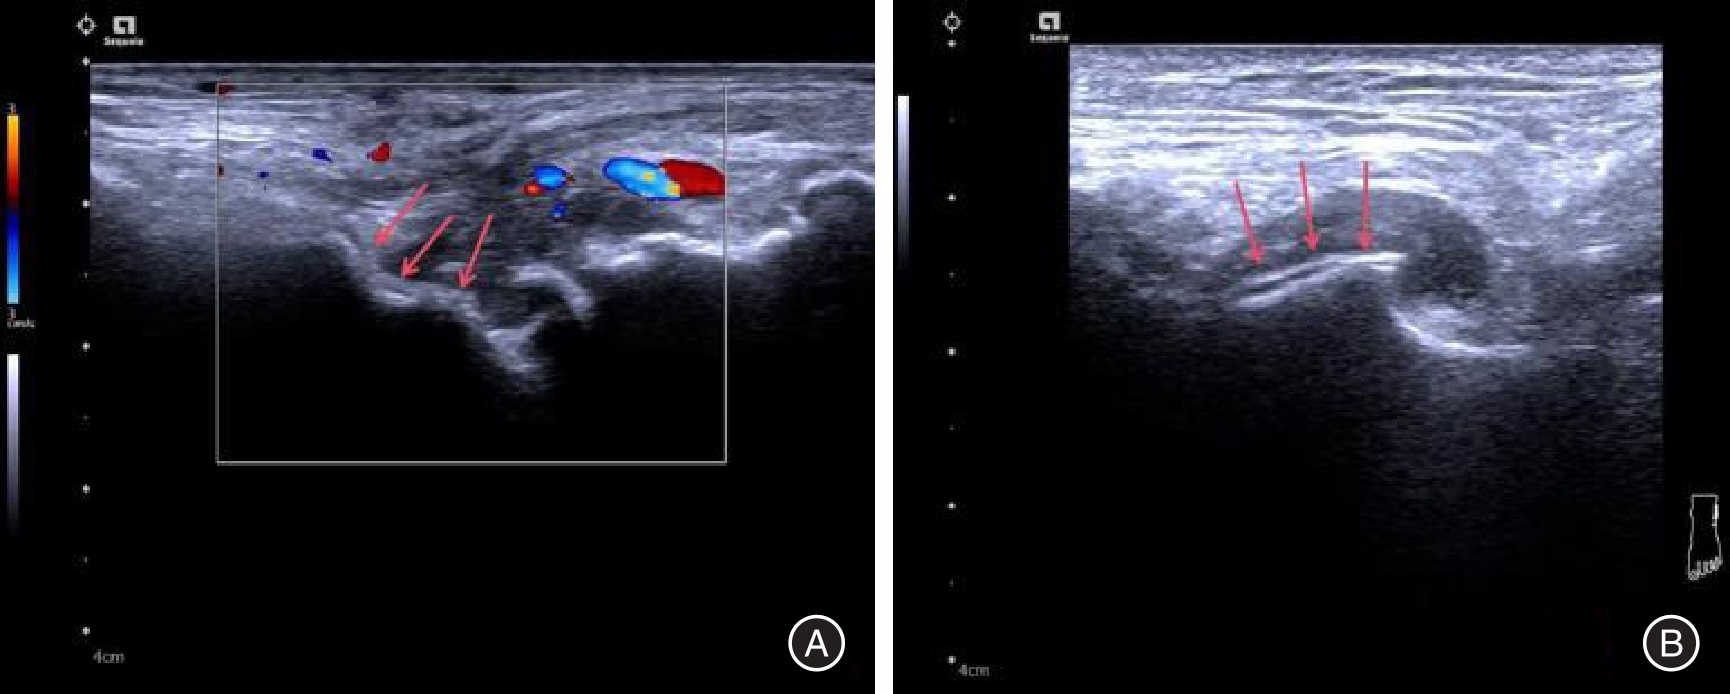

目的 探究双能量CT联合肌骨超声鉴别诊断焦磷酸钙沉积病与痛风性关节炎的价值。 方法 回顾性分析痛风性关节炎102例和焦磷酸钙沉积病102例患者的病历资料,分别记为痛风组和钙沉积组。所有患者均行双能量CT和肌骨超声检查,并以关节滑液或关节腔内晶体物质的穿刺结果作为金标准。评估双能量CT、肌骨超声诊断焦磷酸钙沉积病与痛风性关节炎的效能。 结果 痛风组患者的男性比例、血尿酸均高于钙沉积组(P < 0.05)。痛风组患者中膝关节、第一跖趾关节、踝关节的受累率偏高,钙沉积组患者中膝关节、腕关节、肩关节的受累率偏高。痛风组患者的骨皮质不规则、软骨损伤、半月板退行性变的所占比例均低于钙沉积组(P < 0.05)。痛风组患者的双轨征、痛风石、韧带内强回声、肌腱内强回声、骨侵蚀占比高于钙沉积组(P < 0.05),软骨钙化低于钙沉积组(P < 0.05)。双能量CT、肌骨超声及二者联合诊断焦磷酸钙沉积病和痛风性关节炎的灵敏度分别为86.27%、83.33%、94.12%,特异度分别为89.22%、88.24%、86.27%,阳性预测值分别为88.89%、87.63%、87.27%,阴性预测值分别为86.67%、84.11%、93.63%,准确率分别为87.75%、85.78%、90.20%,一致性Kappa值分别为0.755、0.716、0.804。 结论 双能量CT联合肌骨超声在焦磷酸钙沉积病与痛风性关节炎中的诊断效能良好,可用于辅助鉴别诊断两种疾病。

Objective To investigate the utility of dual?energy CT combined with musculoskeletal ultrasonography in differentiating between calcium pyrophosphate deposition disease and gouty arthritis. Methods A retrospective analysis was conducted on the medical records of 102 patients diagnosed with gouty arthritis and 102 patients diagnosed with calcium pyrophosphate deposition disease. These patients were categorized into the Gout group and Calcium Deposition group, respectively, based on their respective diagnoses. All patients underwent dual?energy CT and musculoskeletal ultrasonography examinations, while joint fluid aspiration results or intra?articular crystal material served as the gold standard for diagnosis. The diagnostic efficacy of dual?energy CT and musculoskeletal ultrasonography in discriminating between calcium pyrophosphate deposition disease and gouty arthritis was evaluated. Results In the gout group, the proportion of male patients and serum uric acid levels were significantly higher compared to those in the calcium deposition group (P < 0.05). The prevalence rates of knee joint, first metatarsophalangeal joint, and ankle joint involvement were higher in the gout group, while knee joint, wrist joint, and shoulder joint involvement rates were higher in the calcium deposition group. The proportions of irregular bone cortex, cartilage injury, and degenerative meniscus changes were lower in the gout group compared to the calcium deposition group (P < 0.05). The proportions of double contour sign, tophus formation, hyperechoic band within ligaments or tendons, and bone erosion were higher in the gout group compared to the calcium deposition group (P < 0.05), whereas cartilage calcification was lower in the gout group (P < 0.05). The sensitivities for diagnosing calcium pyrophosphate deposition disease and gouty arthritis using dual?energy CT scan alone, musculoskeletal ultrasound alone, and their combined use were 86.27%, 83.33%, and 94.12% respectively. The specificities for diagnosing these conditions using dual?energy CT scan alone,musculoskeletal ultrasound alone,and their combined use were 89.22%,88.24%, and 86.27% respectively. The positive predictive values were 88.89%, 87.63%, and 87.27%, respectively. The negative predictive values were 86.67%, 84.11%, and 93.63%, respectively. The accuracies were 87.75%, 85.78%, and 90.20% respectively. The agreement Kappa values were 0.755, 0.716, and 0.804 respectively. Conclusions The integration of dual?energy CT and musculoskeletal ultrasonography exhibits promising diagnostic efficacy in discriminating between calcium pyrophosphate deposition disease and gouty arthritis. This combined approach serves as a valuable adjunctive tool for the diagnosis of both conditions.